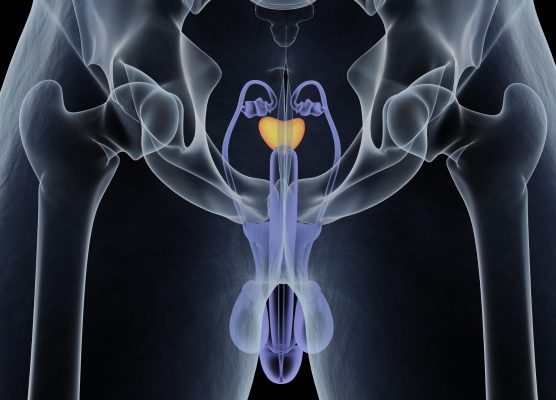

Λίγα εκπαιδευτικά χειρουργικά βίντεο υψηλής ποιότητας είναι διαθέσιμα για την εξάτμιση του προστάτη με λέιζερ πράσινου φωτός για την καλοήθη υπερπλασία του προστάτη, σύμφωνα με μια μελέτη που δημοσιεύτηκε στο τεύχος Δεκεμβρίου του Translational Andrology and Urology.

Ο Shi-Qin Yang, από το Πανεπιστήμιο Sichuan στο Chengdu της Κίνας, και οι συνεργάτες του εξέτασαν την εκπαιδευτική αξία των βίντεο του YouTube σχετικά με τη φωτοεκλεκτική εξάτμιση του προστάτη για καλοήθη υπερπλασία του προστάτη. Για την αξιολόγηση της εκπαιδευτικής αξίας, αναπτύχθηκε μια λίστα ελέγχου που περιλαμβάνει τέσσερα κύρια και 16 δευτερεύοντα στοιχεία. Αξιολογήθηκαν εβδομήντα τέσσερα χειρουργικά βίντεο (μέση διάρκεια, 12,69 λεπτά).

Για εκπαιδευτικά βίντεο, ο μέσος αριθμός ημερών που ήταν διαθέσιμες στο διαδίκτυο ήταν 2.607, με τα παλαιότερα βίντεο να χρονολογούνται από το 2006 και τα τελευταία βίντεο από το 2021. Ο ορισμός βίντεο ταξινομήθηκε ως υψηλός, μέτριος και χαμηλός, αντιπροσωπεύοντας το 21,6, 66,2 και 12,2 τοις εκατό, αντίστοιχα . Ο μέσος αριθμός των “μου αρέσει” ήταν 34,26 και ο μέσος αριθμός “δεν μου αρέσει” ήταν 0. Οι ερευνητές διαπίστωσαν ότι η μέση βαθμολογία βίντεο ήταν 6,65 (εύρος, 2 έως 12). Μόνο το 24,3 τοις εκατό των βίντεο έδωσαν έμφαση στα κρίσιμα βήματα της επέμβασης. Ο αριθμός των προβολών βίντεο σχετιζόταν με τον αριθμό των ημερών στο διαδίκτυο και των επισημάνσεων “μου αρέσει”. Οι βαθμολογίες βίντεο σχετίζονταν με τον αριθμό των “μου αρέσει” και παρατηρήθηκε συσχέτιση για τον ετήσιο μέσο αριθμό προβολών με τον αριθμό των προβολών και τον αριθμό των “μου αρέσει”.

«Το YouTube δεν διαθέτει υψηλής ποιότητας εκπαιδευτικά χειρουργικά βίντεο για την πράσινη εξάτμιση του προστάτη με λέιζερ και χρειάζονται πιο λεπτομερείς εξηγήσεις για τα βασικά βήματα της επέμβασης», γράφουν οι συγγραφείς. “Ελπίζουμε ότι περισσότερα βίντεο με υψηλότερη εκπαιδευτική αξία μπορούν να δημοσιευτούν στο μέλλον για να βοηθήσουν τους αρχάριους να κατακτήσουν αυτήν την τεχνολογία.”